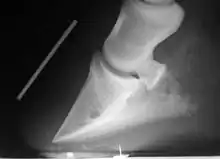

Bascule de la troisième phalange.

La fourbure est une congestion inflammatoire aiguë du pied. En raison de l'inextensibilité relative de la boîte cornée, elle entraîne un arrêt circulatoire localisé avec ischémie des tissus, notamment du tissu kéraphylleux. Il se produit une désunion entre les structures osseuses et cornées, provoquant non pas le basculement de la troisième phalange vers l'avant car l'os naviculaire placé derrière l'en empêche, mais par le décollement de la paroi, caractéristique de cette affection. À l'extrême, la troisième phalange peut perforer la sole[5]. Il s'agit là d'un cas gravissime.

La cause peut être métabolique (par excès de nourriture, déshydratation, infections généralisées provoquant la libération d'endotoxines ou rétention placentaire), traumatique (par excès de travail ou surcharge chronique, c'est-à-dire par excès de poids) ou iatrogène (administration de trop grande quantité de corticoïdes). Une fourbure chronique peut se manifester à la suite d'une fourbure aiguë[65].

Le traitement est celui de la cause avec, de plus, mise au repos, anti-inflammatoires non stéroïdiens (les corticoïdes sont à proscrire), avec ferrure orthopédique s'il est possible de mettre en place un fer en tronquant la pince et en privilégiant l'appui sur les talons(fer à l’envers, fer ovale, ou si phalange distale est déplacée, un fer en cœur ou un fer en M)[66]. Une plaque et du silicone peuvent être également mises en place. Dans les suivis possibles, citons également l'administration d'acépromazine, le patch de nitroglycérine ou la cryothérapie pour la vasodilatation, la mise en place d'une litière épaisse au box, ou encore la saignée dans les 12 heures après les premiers symptômes en cas de surcharge alimentaire[65]. Des inhibiteurs du TNF sont parfois utilisés[59].